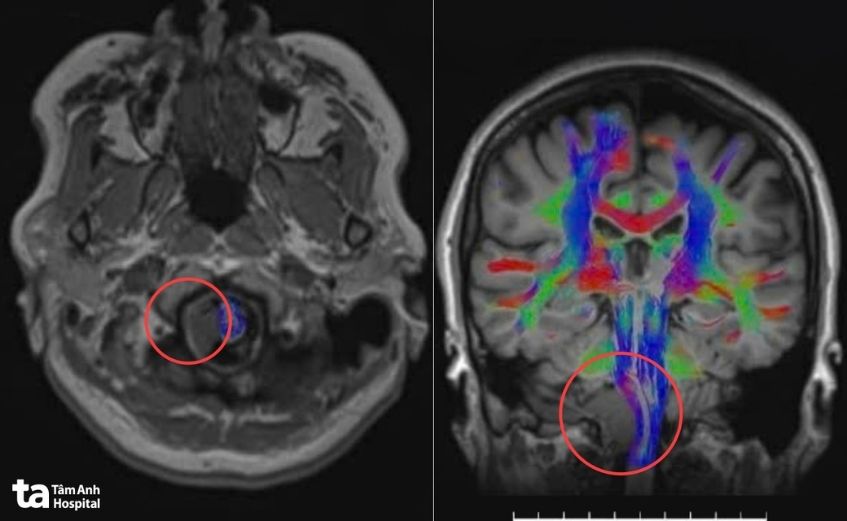

Ban đầu, bà Hạnh tê vùng lưỡi, đau đầu vùng chẩm đi khám phát hiện khối u não kích thước 2,5 cm ở vùng góc hành – tiểu não phải, chèn ép các dây thần kinh sọ thấp 9, 10, 11, 12. Đây là nhóm dây thần kinh điều khiển hoạt động nuốt, nói, cử động lưỡi, cơ cổ và động mạch cột sống.

Trước khi mổ, robot AI sử dụng công nghệ hòa hình đa lớp, tích hợp dữ liệu từ MRI và CT để tái tạo mô hình não 3D với độ phân giải cao. Nhờ đó, êkíp xác định rõ vị trí, kích thước cũng như mối liên quan giữa khối u và các dây thần kinh sọ 9, 10, 11, 12 cùng mạch máu nền sọ, lập kế hoạch tiếp cận tối ưu qua cửa sổ C1 – vùng nối giữa cổ và nền sọ.